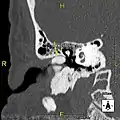

Exostosis in ear canal

The normal ear canal is approximately 7 mm in diameter and has a volume of approximately 0.8 ml (approximately one-sixth of a teaspoon).[4] As the condition progresses, the diameter narrows and can even close completely if untreated, although people generally seek help once the passage has constricted to 0.5–2 mm due to the noticeable hearing impairment. While not necessarily harmful in and of itself, constriction of the ear canal from these growths can trap debris, leading to painful and difficult to treat infections.